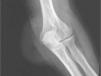

Presentamos un caso de bursitis olecraniana por Eggerthella lenta en un varón de 70 años con antecedentes de: accidente cerebrovascular, hipertensión arterial, hiperuricemia, insuficiencia renal crónica leve por nefroangiosclerosis, cardiopatía isquémica, estenosis carotídea bilateral, artritis reumatoide resistente al tratamiento con etanercept y corticoides y bursitis olecraniana crónica de origen mecánico. Presenta nódulos reumatoideos en ambas bursas olecranianas de larga evolución, por este motivo fue intervenido en el codo derecho varios años atrás. Acude a consulta por tumefacción en la región olecraniana derecha, sin fiebre ni escalofríos. Se le practica bursocentesis en bursa olecraniana, y se obtiene líquido sinovial de características inflamatorias, sin evidencia de microcristales al microscopio óptico de luz polarizada. Se envía la muestra para cultivo en frasco de hemocultivo de aerobios (Bact-Alert, Organon-Technika), que resulta negativo a los 5 días de incubación. Cuatro días más tarde regresa a la consulta por empeoramiento, y en la exploración física presenta tumefacción, aumento de la temperatura local, eritema y dolor a la palpación. Presión arterial, 124/84; temperatura, 36,4°C. Analítica de sangre con 9.960 leucocitos/μl, con el 76,4% de neutrófilos, el 15% linfocitos; velocidad de sedimentación globular, 19mm la primera hora; proteína C reactiva, 0,53mg/dl. En la radiografía de codo derecho se observa importante aumento de partes blandas en la zona posteromedial (figs. 1 y 2), con imágenes radiolúcidas en su interior. Se repite la bursocentesis y se obtiene líquido sinovial de aspecto macroscópico purulento, que se envía al servicio de microbiología para cultivo en jeringa estéril y en frascos de hemocultivos para crecimiento de aerobios y anaerobios. La tinción de Gram muestra abundantes leucocitos polimorfonucleares y bacilos grampositivos intracelulares. Se inicia tratamiento con amoxicilina-clavulánico 1g/8h i.v. A las 48 horas se positiviza el frasco de hemocultivo anaerobio, y se hacen subcultivos en agar sangre, agar chocolate (5% CO2), agar Sabouraud y agar Schaedler (anaerobiosis); en esta última placa, se observa el crecimiento de un bacilo grampositivo, identificado por galería Api 20 A (BioMérieux) como Eubacterium lentum (actualmente, E. lenta)5. Las pruebas de sensibilidad a antimicrobianos se realizaron con tiras de E-test (ABBiodisk, Solna, Suecia) en agar Brucella, y fue sensible a penicilina G, amoxicilina-clavulánico, cefoxitina, imipenem, clindamicina y metronidazol. Se extraen muestras de líquido sinovial diariamente, que resultaron positivas los tres días posteriores al ingreso, momento en que se negativizan.